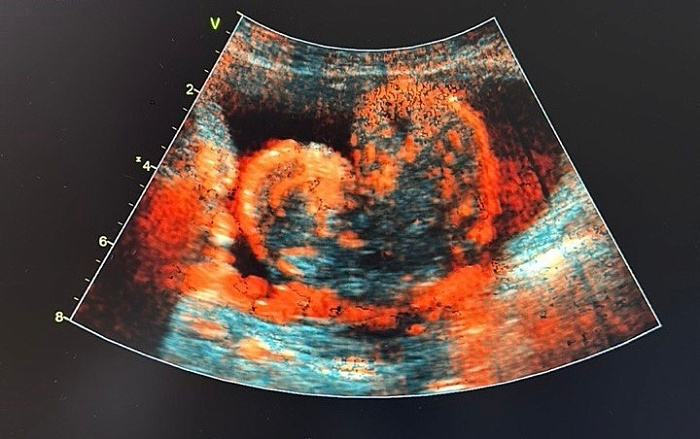

В онкодиспансере Бурятии обнаружили опухоль в форме сердца. Необычным снимком поделились врачи, проводившие УЗИ простаты.

Как сообщили в учреждении, опухоль выросла из простаты. Примечательно и то, что она была обнаружена во время осмотра 14 февраля, в День всех влюбленных.